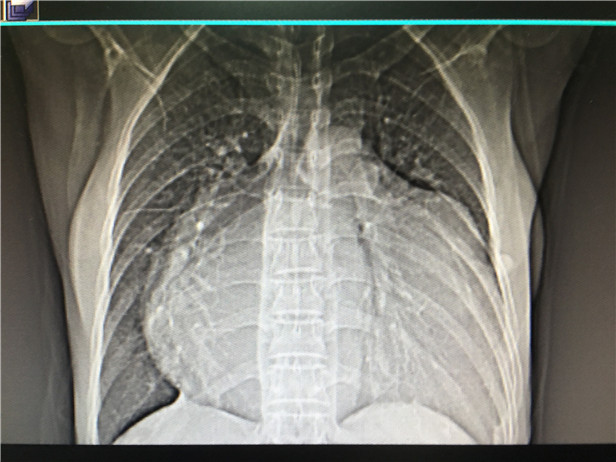

(术前的心脏照片)

意识到严重后,夫妻俩才又赶往黎平县中医院进行检查。这次,诊断结果连医生都被吓了一跳,“她的心脏是正常人的2倍,膨胀得像足球一样大,几乎占满了左右胸腔,情况十分危急,必须立即转院接受治疗。”医生们建议道。

心血管外科主治医生吴昊告诉记者说,由于患者的病情拖延了12年,术前检查发现其左房内径为80mm(正常值20—33)可见,心房几乎增大了一倍,情况非常危急,手术难度非常大,最坏的结果很有可能患者无法走下手术台。

事后,在徐平教授近5小时的努力下,患者吴女士异常增大的心脏缩小了1/2,成功完成了“瘦身”。术后,吴女士各种不适症状消失,心功能逐渐改善,目前已能够下床活动。